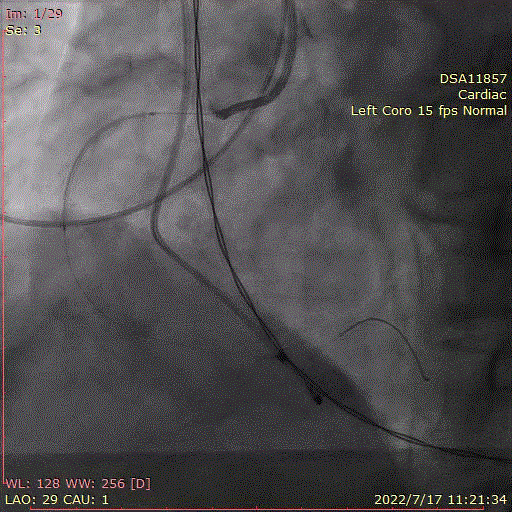

术中首先行冠脉造影术,造影提示右冠近中段严重狭窄,于病变处植入支架一枚。植入后造影显示,无残余狭窄及夹层,前向血流TIMI3级。

冠脉造影,支架植入